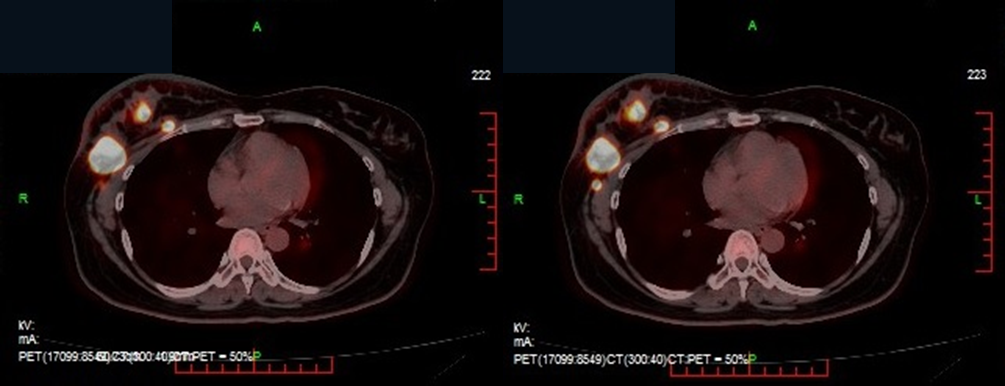

PET/CT(2023.01.04):提示右乳多发高代谢癌灶,并广泛转移至右侧腋窝、纵膈、肺门等多处淋巴结,同时伴有双肺及右侧胸膜转移。

诊断:右乳浸润性导管癌IV期(cT2N3M1 LuminalB型 HER-2 low)、多发淋巴结转移、双肺多转移瘤、右侧胸膜转移